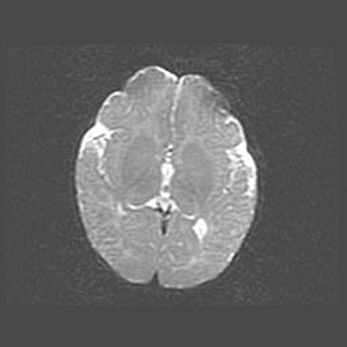

Множественные кисты обоих полушарий головного мозга, наибольшая из них в правой затылочной области. Ассиметричная атрофическая гидроцефалия.

Возраст: 7 месяцев

Вес: 5660 г

Пол: мужской

Окружность головы: 41,5 см

Срок гестации: 28-29 недель

Кисты головного мозга развиваются в результате многоочаговых некрозов вещества мозга и возникают вследствие перенесенной перинатальной инфекции, менингитов, энцефалитов, асфиксии, родовой травмы, расстройств мозгового кровообращения различного генеза. Образованию кист в веществе головного мозга плодов и новорожденных способствуют такие факторы, как высокое содержание в нем воды, недостаточная (или отсутствие) миелинизация и слабая астроглиальная реакция на повреждение.

Кисты могут сочетаться с гидроцефалией и другими поражениями головного мозга.